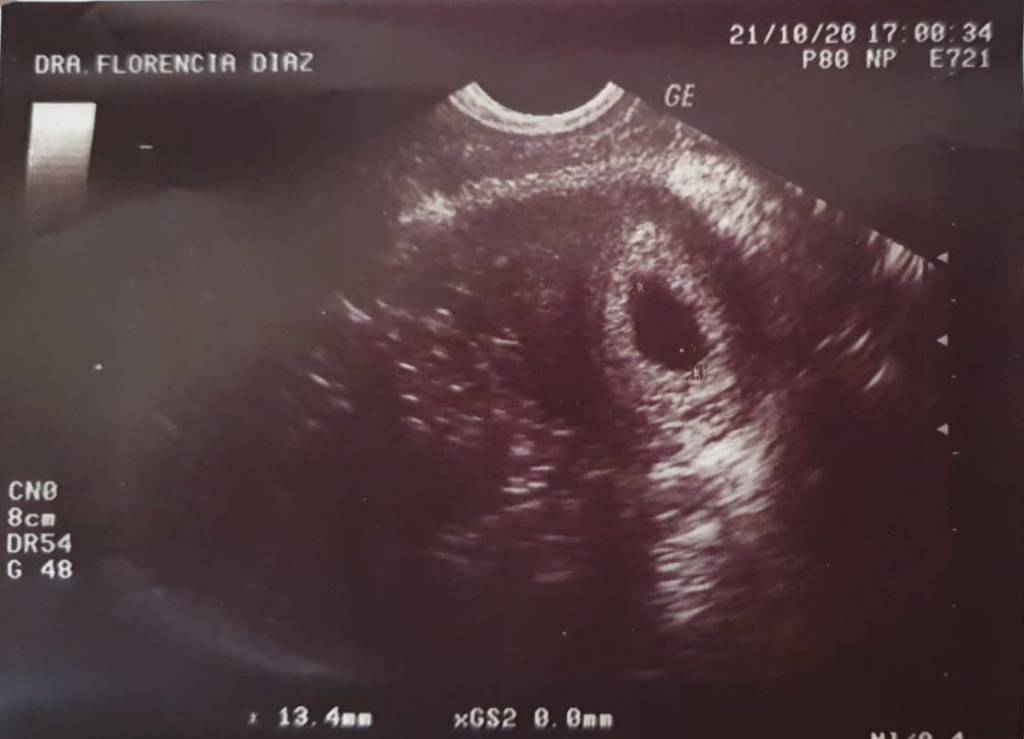

Cuando recibí la noticia de que sería abuela, fue de una manera bonita y sencilla. Mi hija y su novio me entregaron una cajita en la que venia un poema y la primera foto del bebé, eso fue hace casi once semanas y no puedo explicar cuánto ha cambiado mi vida y mis emociones en tan solo unas pocas semanas.